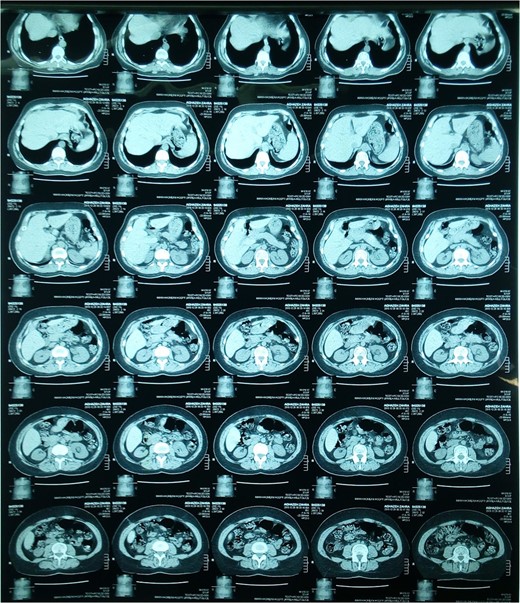

The patient was a 51-year-old lady with left flank colicky pain accompanied with nausea and vomiting for a month. Transurethral lithotripsy and ureteral stent placement was considered for the patient. The patient had a narrow ureteral lumen and while bringing the ureteroscope out, ureteral avulsion occurred at a distance approximately 4 cm from ureteropelvic junction. After bringing the uretroscope out, the avulsed ureter was observed hanging at the tip of the ureteroscope. Anastomosis of the ureter to the bladder was accomplished with Lich–Gregoir technique. A drainage tube was inserted at the site of incision and the surgical wound closed. The patient was discharged with acceptable general condition after 3 days and the drainage tube removed. The ureteral stent was removed 4 weeks later by cystoscopy. An ultrasound imaging study of the genitourinary system 8 months into the patients follow up showed normal size, echo and cortical thickness in the operated kidney after renal autotransplantation.

A ureteral catheter was inserted. A drainage tube was inserted to drain any possible bleeding from the operation site and then the surgical wound was closed. The patient was discharged in a good general condition after 3 days and the drainage tube removed. The ureteral stent was removed 4 weeks later by cystoscopy under local analgesia. An ultrasound imaging study of the genitourinary system 8 months into the patients follow up showed normal size, echo and cortical thickness in the operated kidney after renal autotransplantation.